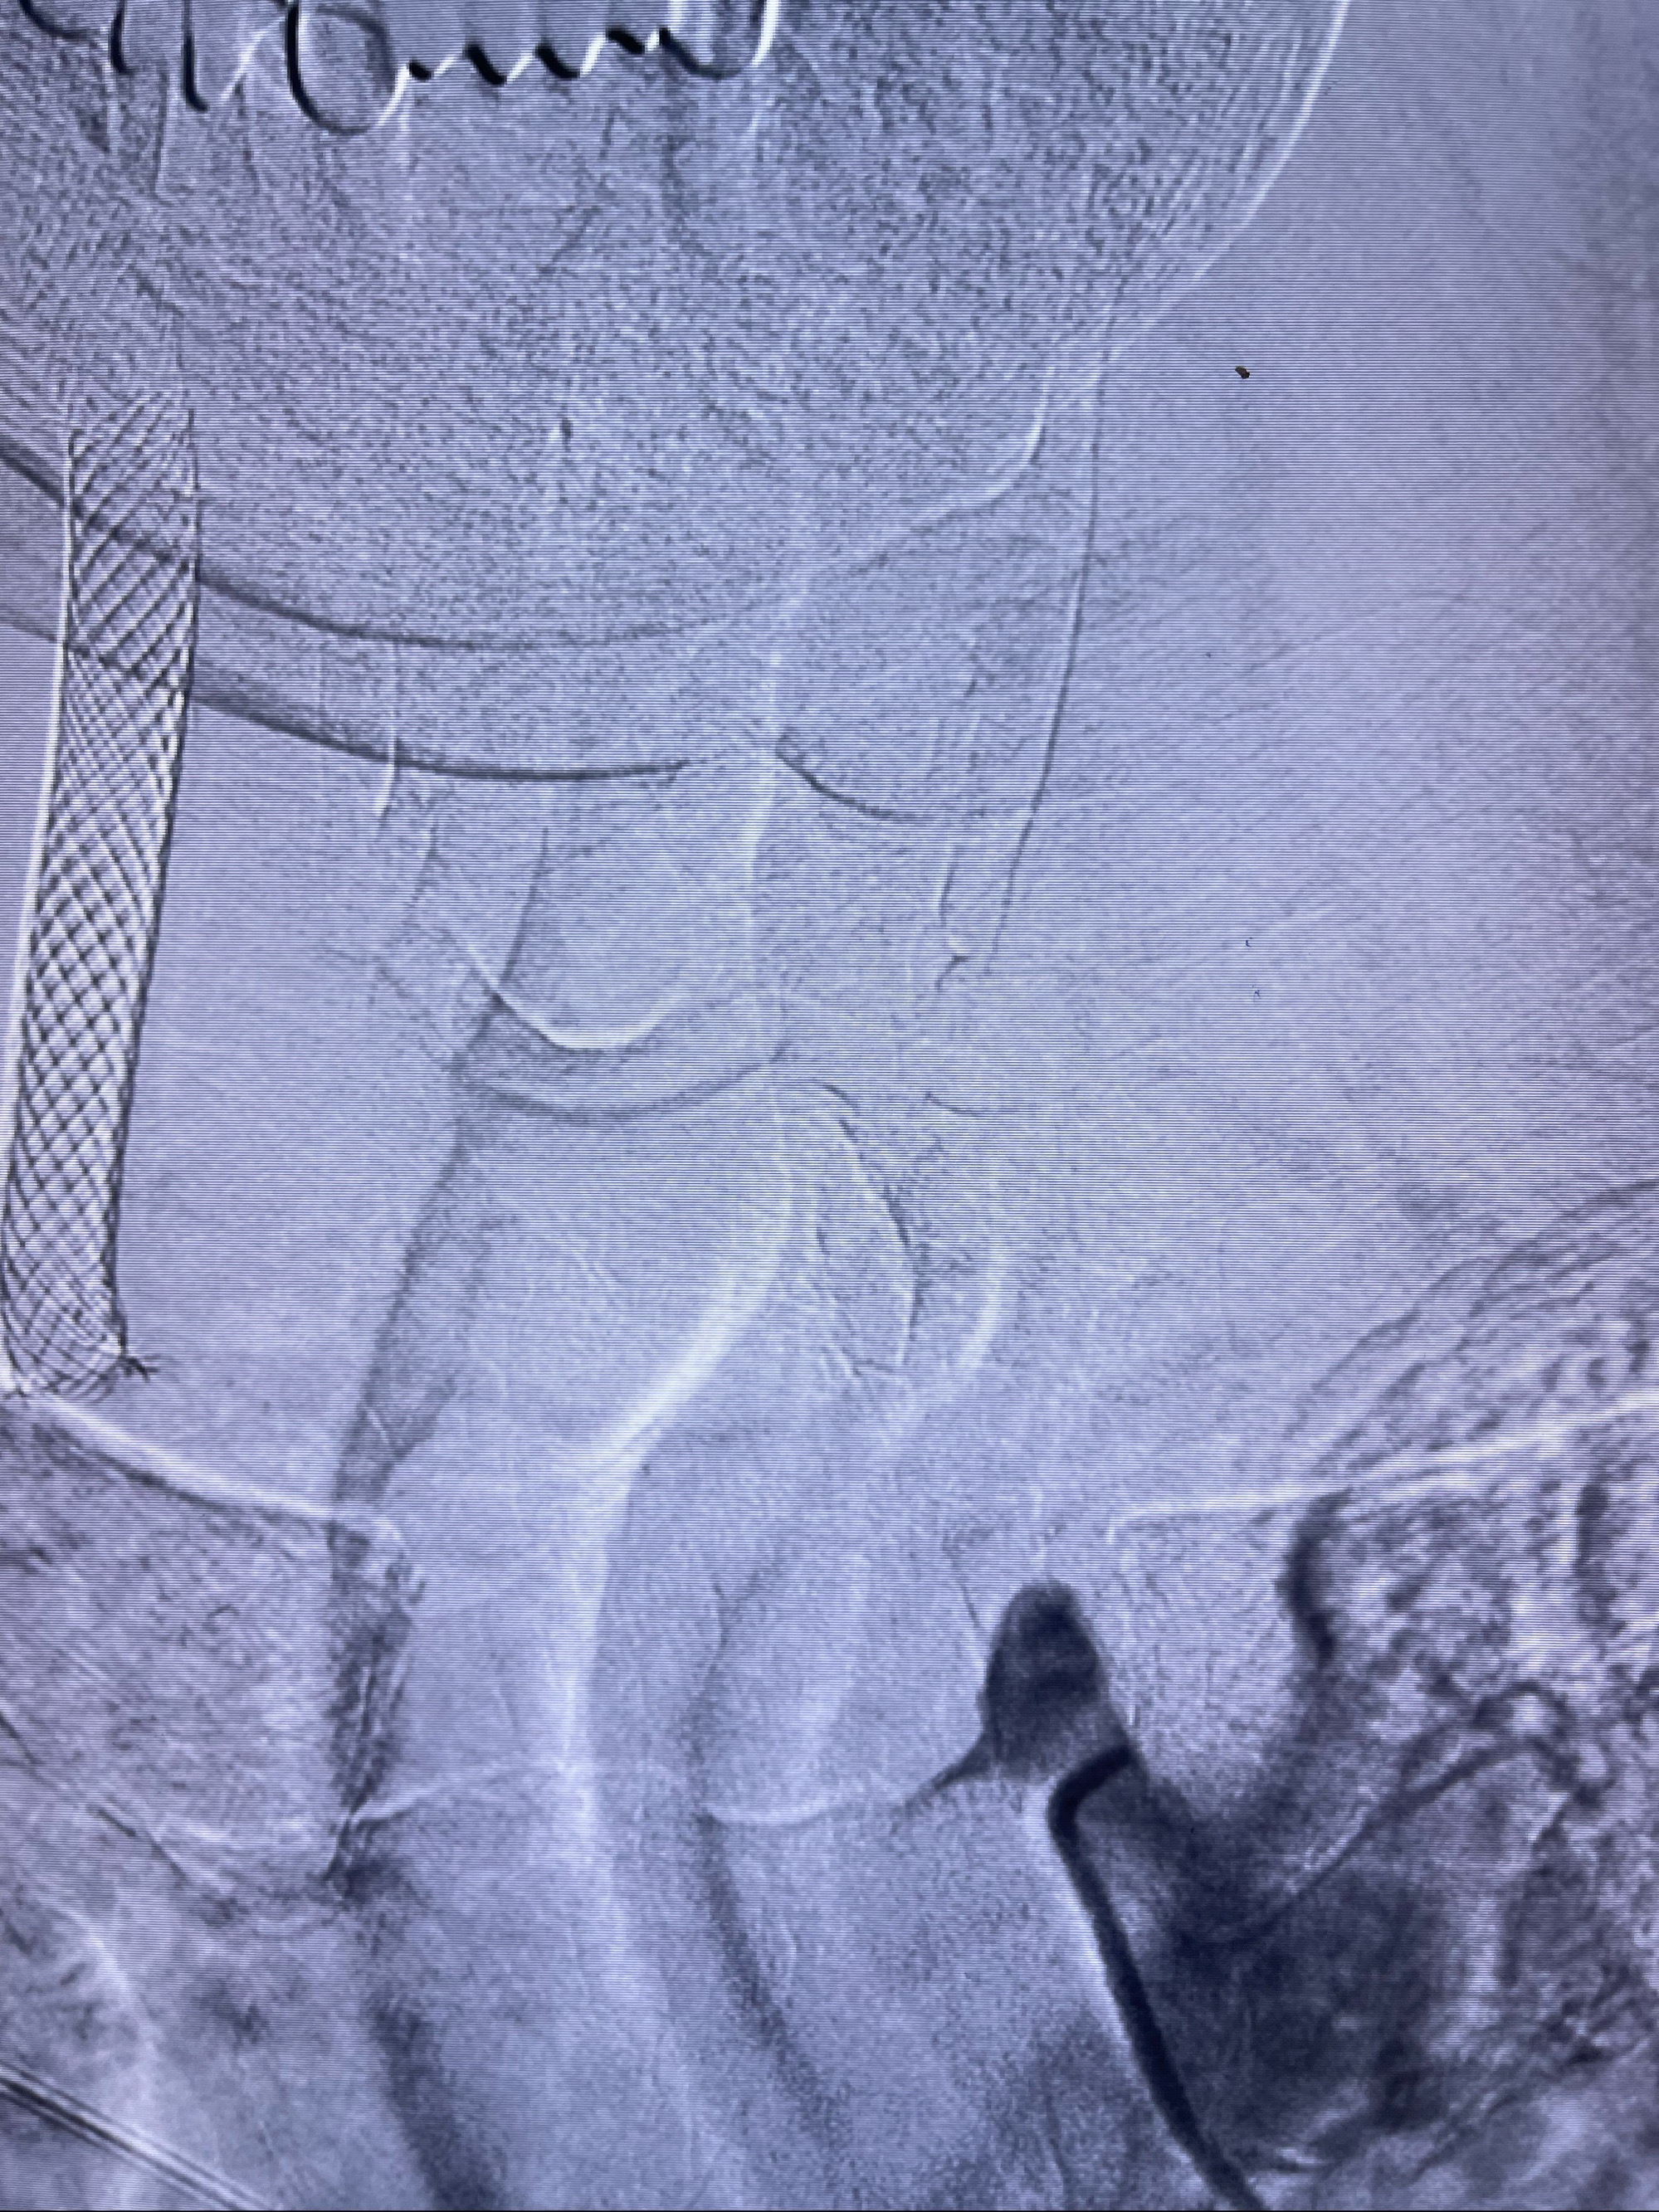

088NeuroMAX100cm长鞘在125cmMPA及黑泥鳅导丝引导下超选择性插入右侧颈内动脉支架内

经导引导管造影显示支架远端颈内动脉不规则狭窄伴局部充盈缺损,同时行全身肝素化5ml

路径图下4-20mm球囊在导丝引导下超选择性至狭窄段,以6-8个大气压扩张,持续30s

泄除球囊造影显示局部管腔扩张佳

后移球囊至颈段狭窄段,以8-12个大气压扩张,持续30s后泄除球囊

即刻造影显示狭窄扩张佳